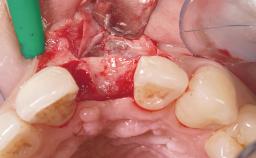

Early Placement of an Implant in a Maxillary Right Central Incisor Site

| Bone Augmentation | Horizontal|Simultaneous |

| Augmentation Materials | Autogenous chips|Xenogenous|Membrane |